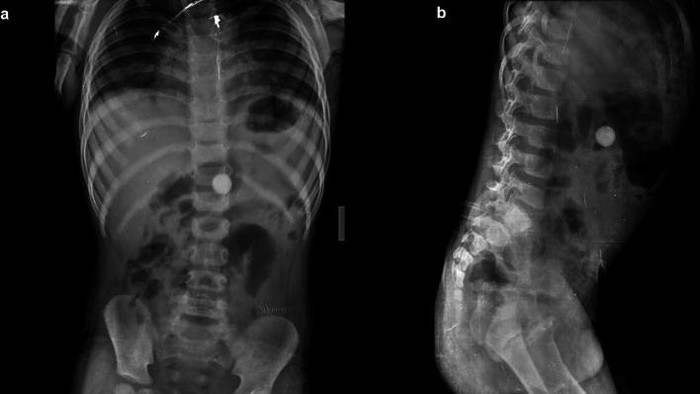

Seorang pria 25 tahun datang menjalani pemeriksaan USG dengan keluhan nyeri perut selama 2-3 bulan. Setelah dilakukan CT scan, dokter menemukan benda logam dalam perutnya. Saat dilakukan laparoskopi, ditemukan banyak isi ulang pulpen dan kawat di dalam lambung pasien. (Foto: F1000 Research)